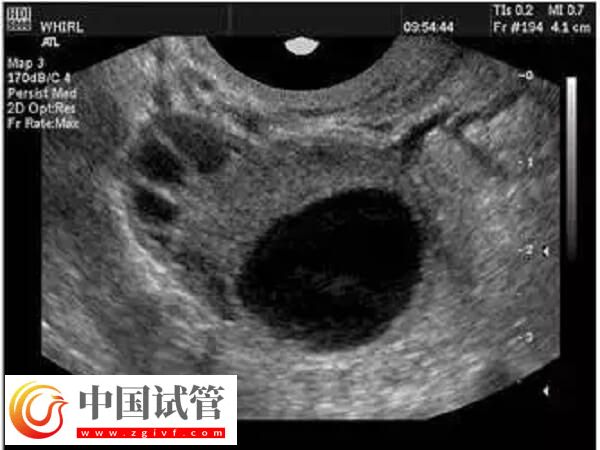

正常情况下,女性每个月只会有一个成熟的卵子形成并排出,然后和精子进行结合。试管婴儿为了进一步提高成功率,往往都会经历促排卵阶段,促使女性卵巢中的多个卵泡同时发育成熟,然后进行取卵,取卵的数量和质量关系到试管的成功率。下面给大家分析一下取卵出现异形卵子的原因:

病理因素也可能导致卵子形态异常,如果女性患有异位妊娠、子宫内膜异位症、子宫肌瘤、卵巢囊肿、卵巢结核等疾病,都有可能出现异形卵子。